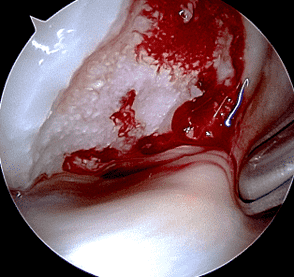

Articular cartilage is susceptible to both traumatic and degenerative lesions, but restoration procedures work best for traumatic lesions. Direct impaction, shear, and twisting mechanisms can injure the articular cartilage.3 Traumatic lesions include chondral fractures, which have a characteristic appearance on MRI characterized by a sharp transition between the lesion and surrounding normal cartilage with the walls of the defect oriented perpendicular to the articular surface (Figures 3A and 3B). Defects are often full thickness, extending to the subchondral bone plate. Subchondral marrow edema is common.4 An unstable cartilage fragment may be present in the crater or displaced as a loose body in the joint. Chondral flaps appear similar to chondral fractures but remain attached to the surrounding cartilage along one side of the lesion, which can act as a hinged trap door (Figures 3C and 3D). The two types of traumatic lesion often coexist, with a chondral fracture frequently demonstrating unstable flap(s) in its periphery (Figures 3E and 3F).

Figure 3: Examples of cartilage injuries amenable to restoration procedures. (3A) Drawing and (3B) sagittal fat-suppressed fluid-sensitive image showing a chondral fracture with vertical walls perpendicular to the articular surface (arrows), sharply demarcating the crater from the surrounding normal cartilage, and focal subchondral marrow edema (asterisk). (3C) Drawing and (3D) axial fat-suppressed fluid-sensitive image showing a chondral flap with a vertical wall on one side of the lesion (red arrow) and a intact, hinged bridge of cartilage on the other, with a full-thickness defect in between (yellow arrow). (3E) Sagittal T2-weighted image of a combined chondral fracture and flap. The chondral fracture has sharp margins (yellow arrows) with the surrounding intact cartilage, while a delaminating flap (black arrow) is present along the posterior lesion margin. (3F) Corresponding arthroscopic picture. The subchondral bone plate is exposed at the base of the lesion (asterisk), with a delaminating flap in the lesion periphery (arrow). C = normal surrounding cartilage.